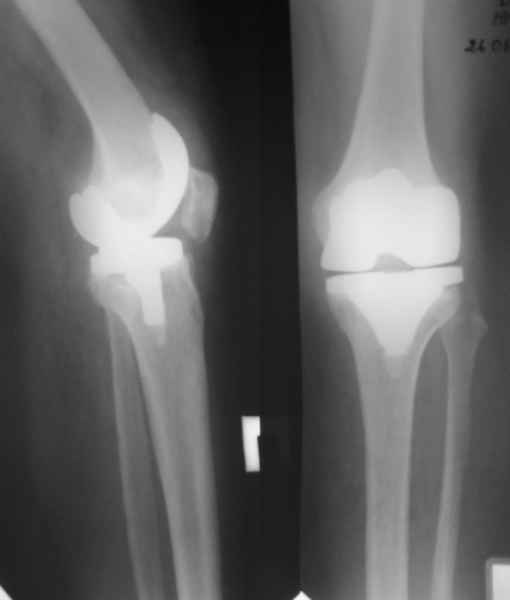

Уважаемые коллеги, Прошу совета. В феврале 2007 года пациентке выполнено эндопротезирование коленного сустава.

13/02/07 |  25/07/07 |  дек. 07 |  25/06/08 |  14/01/09 | Через 1 месяц после операции объем движений 90 градусов, через 2 месяца 60, через 3 - 40, через 5 - качательные движения.

В июле 2007 года выполнена ревизия - полости сустава нет. Капсула сустава имеет толщину от 1 до 1.5 см, собственная связка надколенника имеет толщину до 3 см. Сустав заполнен фиброзно-рубцовой тканью. Компоненты стабильны.

Есть вопросы к установке протеза. Скорее всего тибиальное плато было не конца резецировано и в задненаружных отделах осталась ступенька. Это привело к тому, что тибиальный компонент завалился на варус.

Судя по первому снимку возникает вопрос - а надо было?

Уважаемый Андрей, действительно по снимку до операции сустав кажется сохранным. Но этой пациентке за несколько месяцев до операции была выполнена артроскопия, задокументировано отсутствие хряща на суставных поверхностях внутренних мыщелков бедренной и б\б костей. Этот снимок сделан без нагрузки и поэтому создается впечатление "сохранного сустава". Если бы был сделан снимок до операции с нагрузкой, вашего вопроса не было бы.